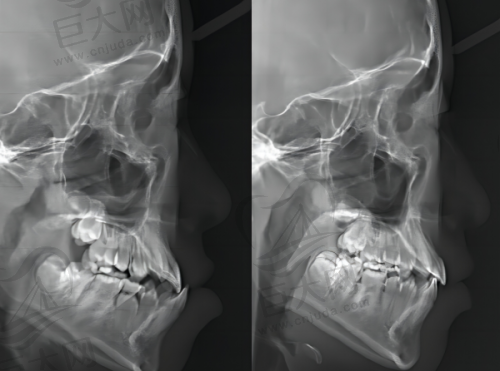

医院引进了数字化种植、即刻种植、自体骨移植等技术,种植过程精细、快速、舒适。医生能够根据患者的具体情况制定个性化的种植方案,满足不同患者的需求。